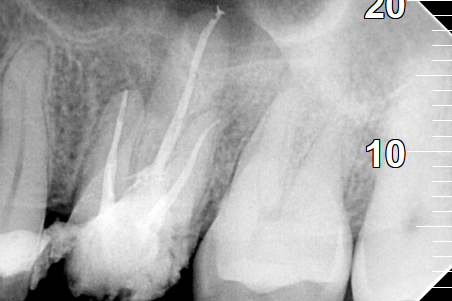

Root canal treatment

BEFORE